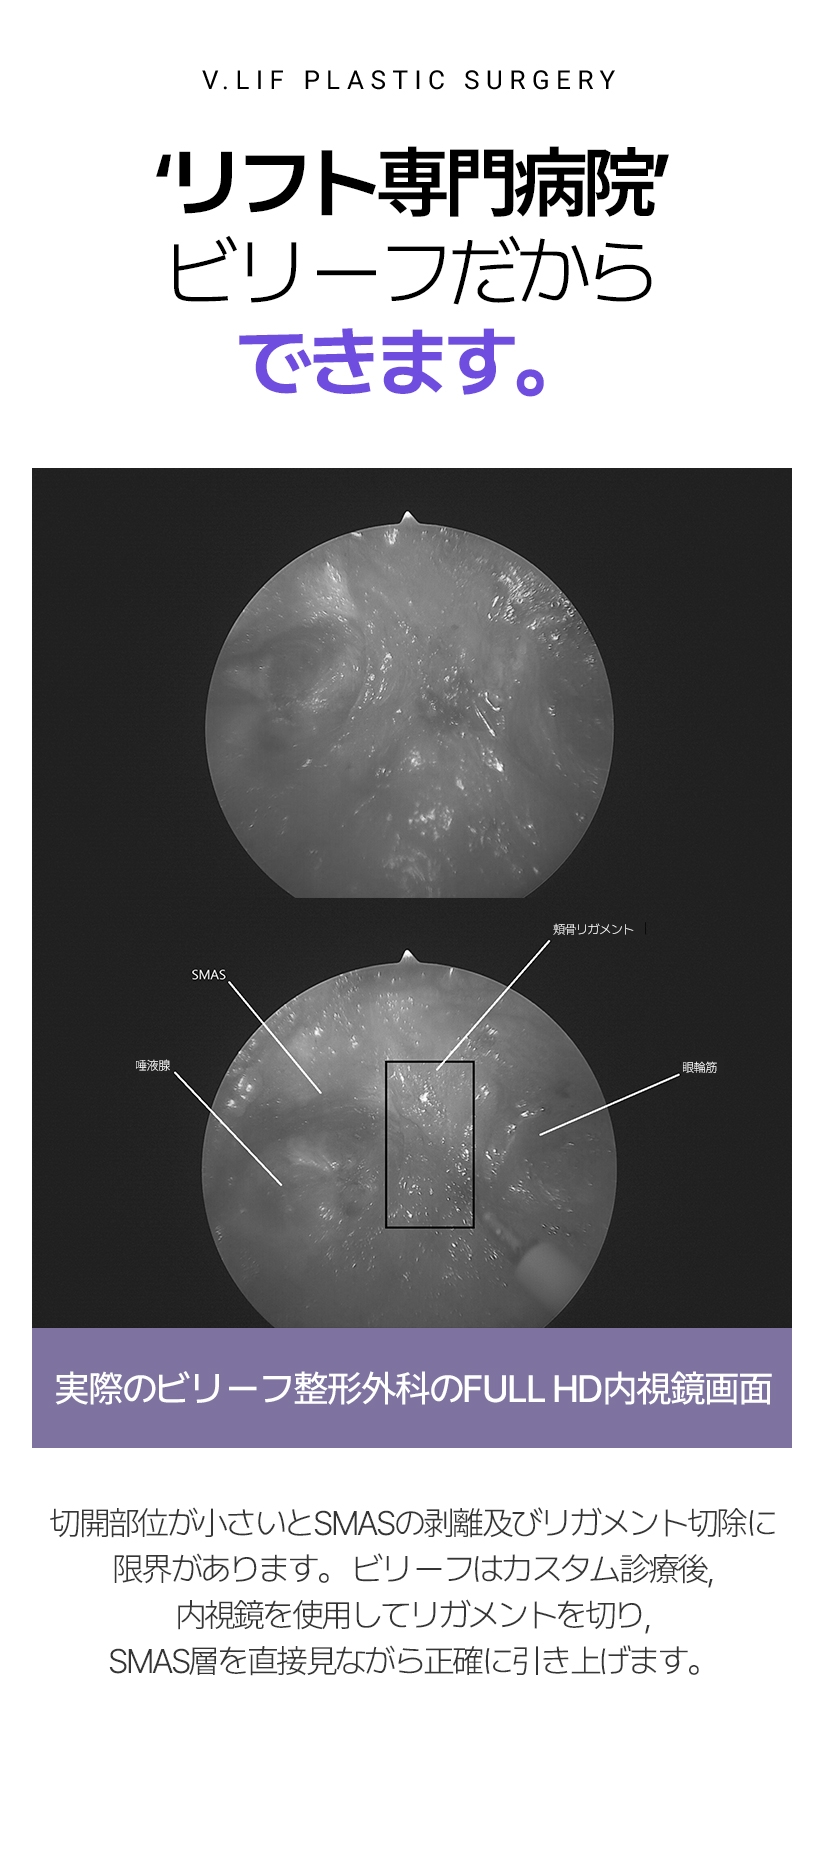

‘リフト専門病院’ ビリーフだからできます。 実際のビリーフ整形外科のFULL HD内視鏡画面 切開部位が小さいとSMASの剥離及びリガメント切除に限界があります。 ビリーフはカスタム診療後, 内視鏡を使用して リガメントを切り, SMAS層を直接見ながら正確に引き上げます。